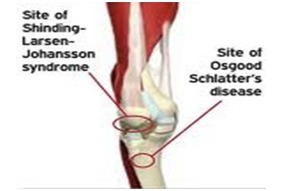

슬패골밑에 있는 경골조면에서만 통증이 나타나고 강합 압통이 주 증상 입니다. 국소적인 열감과 함께 붓는 느낌이 들면서 뼈가 튀어나온 것을 확인할 수 있습니다.

무릎 앞쪽 약간 아래가 아프고 부으면서 무릎 아래에서 뼈가 돌출되는 것이 보인다면 오스굿씨 병 의심해 볼 수 있습니다.

X-ray 검사를 합니다. 성장단계에 따라 크기는 다르지만 경골조면 즉 무릎의 바로 아래에 국한된 골단핵 변화, 유리골편이라는 것이 보여집니다. MRI검사를 하면 연골부를 덮고 있는 슬개건이 두꺼워져 있거나 주변 염증성 변화를 확인할 수 있습니다. 초음파로도 돌출된 뼈와 인대 비후도 볼 수 있습니다.